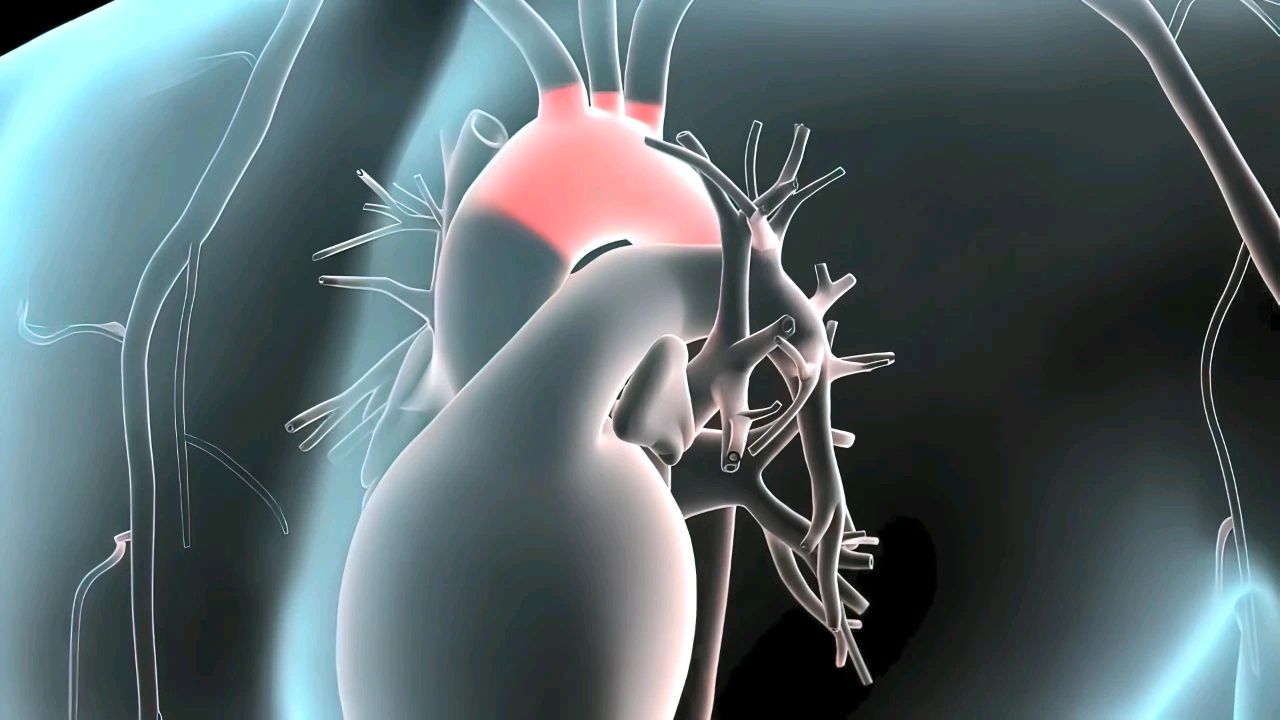

很多人都不把“肚子痛”当回事,总觉得是肠胃出了问题,吃点药就能解决。然而,有一种肚子痛,会在不经意间威胁人的生命。这种“夺命肚痛”的罪魁祸首,就是藏在血管中的“定时炸弹”——主动脉瘤。

这得从主动脉的功能说起。它之所以能承担大量输血的任务,是因为有层厚厚的弹性纤维能以强大的弹性,随心脏舒缩提供血流动力。但随着年龄增长,这些纤维也会老化,血管也变得“脆皮”。如果这时还遭到动脉硬化、高血压、病菌感染等打击纤维会加速老化,让血管壁越来越薄。血管难以承载没日没夜的血液通过,只好被迫扩张膨大,以容纳更多血液,久而久之就胀成瘤样血包一旦瘤体过于庞大(直径≥5cm),脆弱的血管壁受不住压力就可能发生破裂。麻烦的地方就在于在这个早期形成过程中,很多人没有明显症状,等到瘤体扩大到一定程度,感到疼痛才警觉起来。而持续性隐隐作痛,甚至疼痛突然加剧,像被撕裂一样,就说明瘤体有破裂征兆,需要即刻就医。此外,还有一些人会摸到搏动性肿块,随着心脏有节奏地微微颤动,也要及时检查。